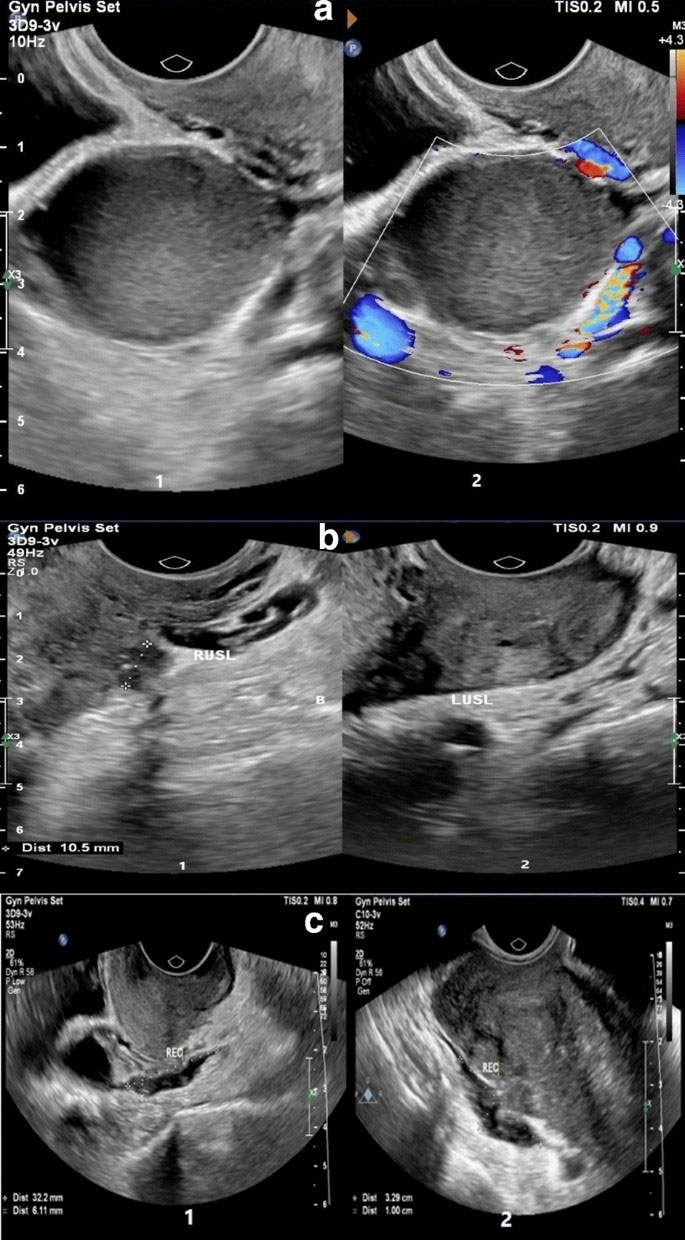

• Ultrasound Imaging: Useful for detecting ovarian endometriomas (chocolate cysts) and other visible abnormalities.

• MRI Scan: Provides enhanced visualization in cases of deep infiltrating endometriosis affecting the bowel, bladder, or ligaments.